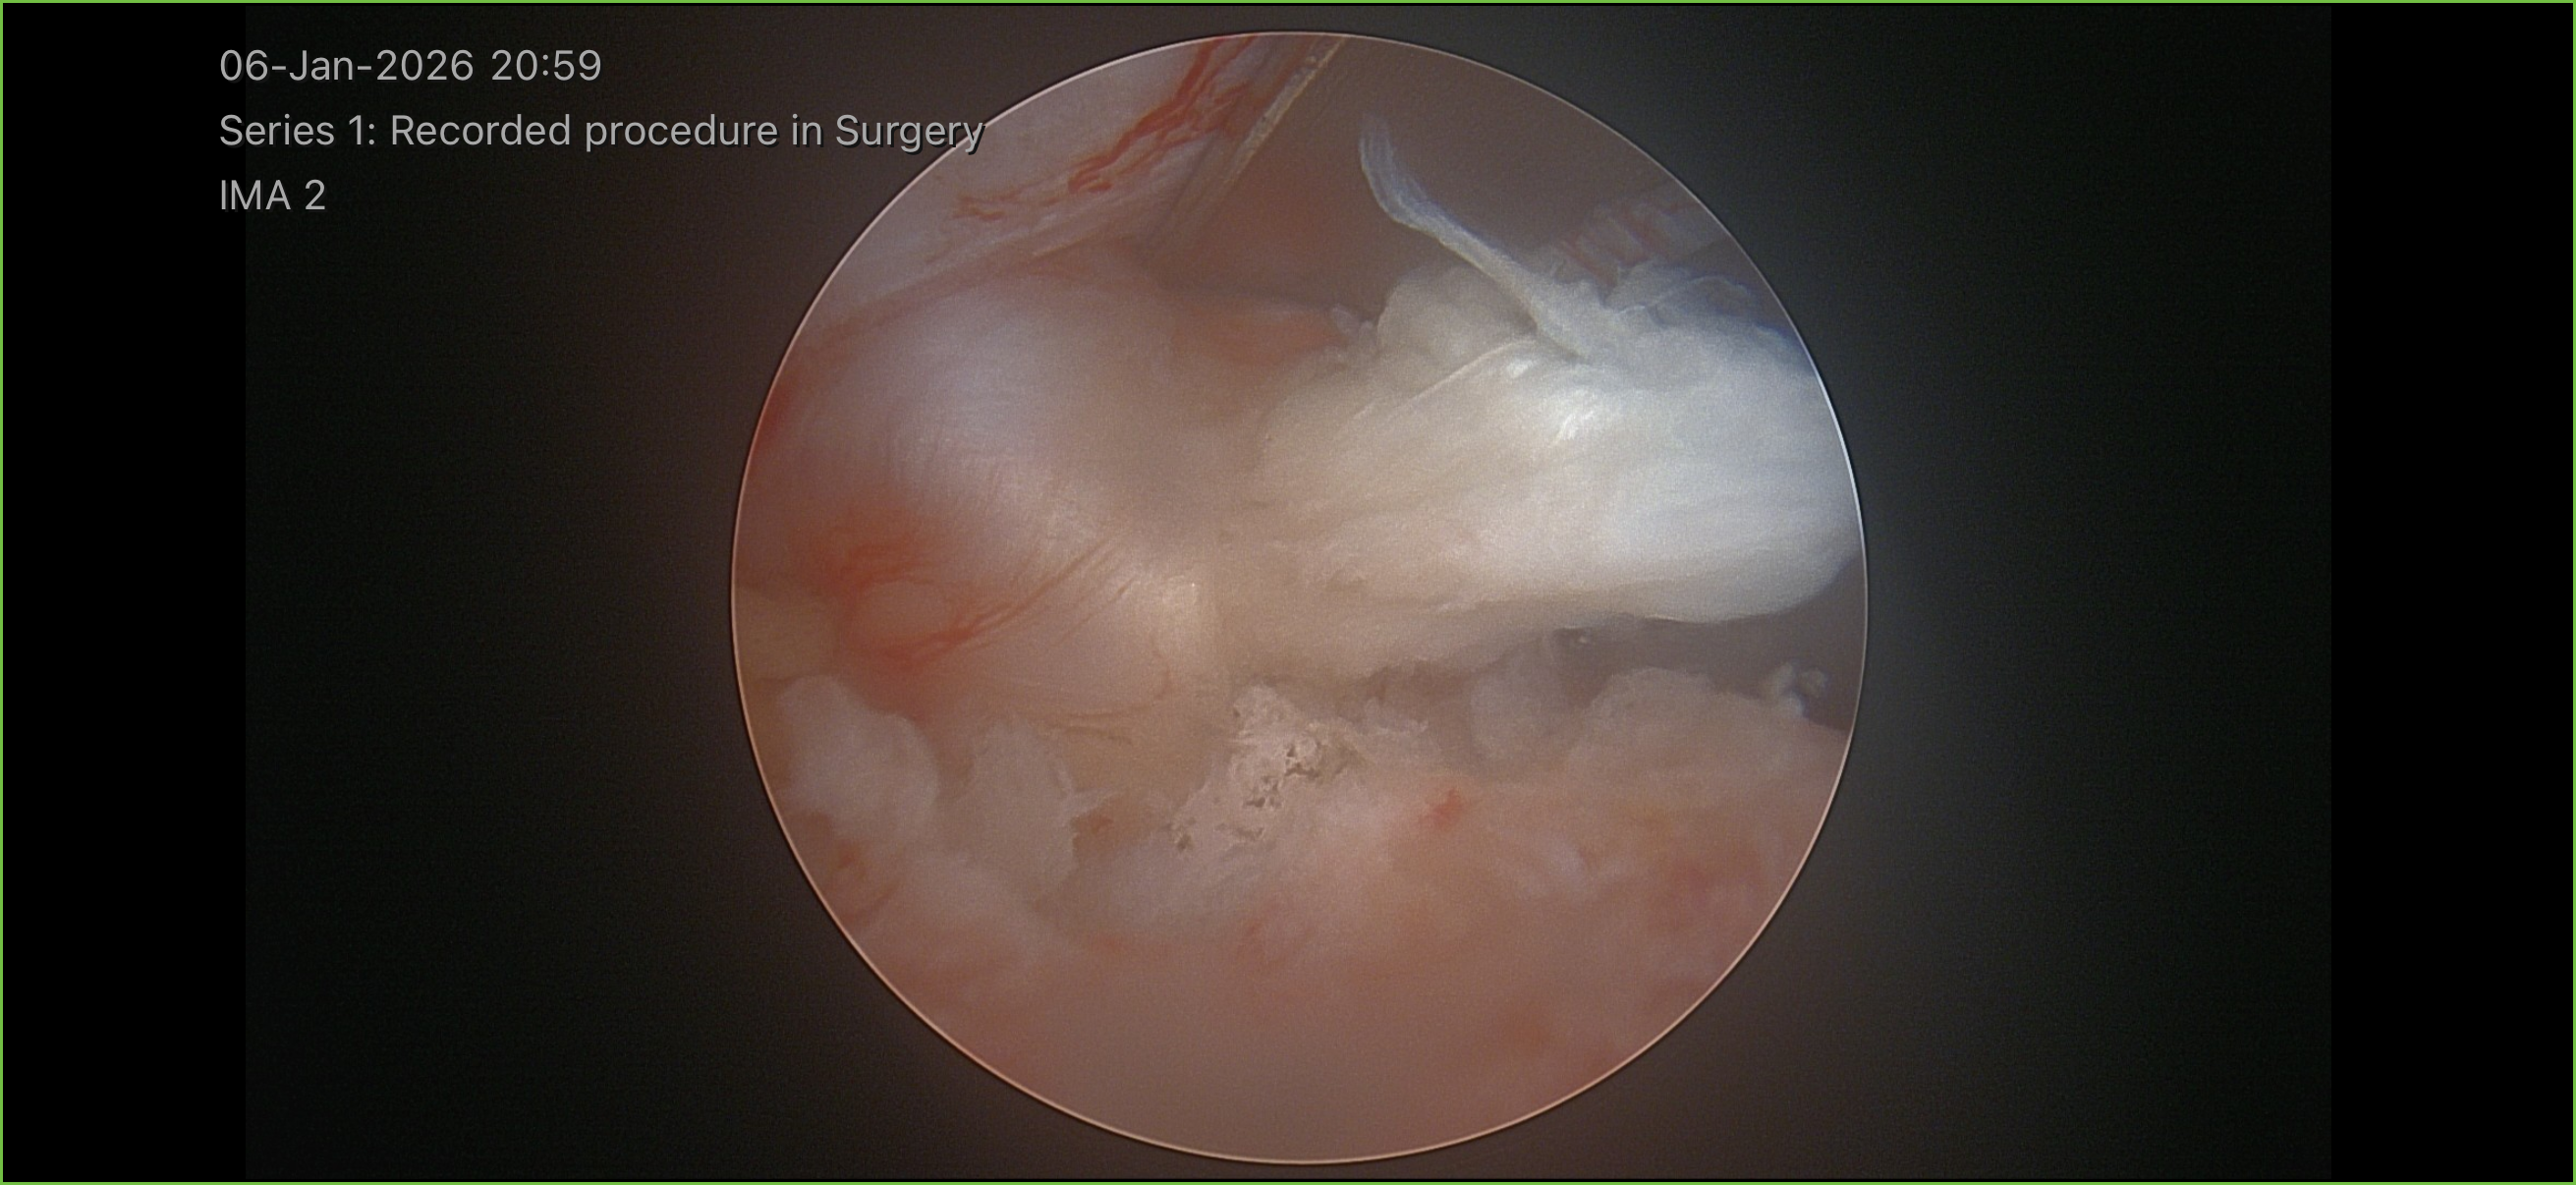

Images & Diagrams

Nerve Decompression

Using specialized micro-instruments through the instrument portal, Dr. Kazarian carefully removes the herniated disc fragment, bone spur, or thickened ligament that is compressing the spinal nerve while viewing the entire procedure through the camera portal. If a laminectomy is needed, a small portion of the lamina bone is precisely removed to widen the spinal canal. The high-definition endoscopic camera provides real-time visualization so Dr. Kazarian can protect the nerve root and surrounding structures with exceptional accuracy. The entire process typically takes 45 to 90 minutes.

Once the nerve is fully decompressed, the endoscope and instruments are removed. The two small incisions are closed with a few stitches or adhesive strips and covered with sterile bandages. You will be taken to the recovery room, where our nursing team will monitor your vital signs, manage any discomfort, and help you begin moving safely. Most patients are able to stand and walk within one to two hours after surgery. Before discharge, your care team will review your pain management plan, activity guidelines, and follow-up appointment schedule with you and your companion.